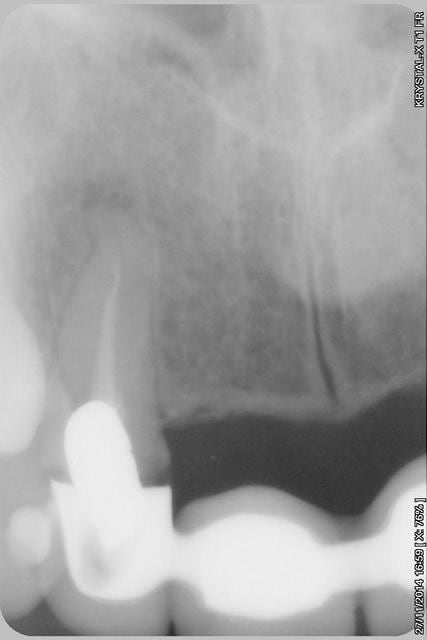

sur-traitement, pompe à fric, assassinat ...etc.. afin d'éviter tout ça je soumet à votre sagesse un cas sympa.

Patiente sympa, 30 ans, un bridge ceramo-métal fait il y a 10 ans, en fin de vie.

Les endo et les IC dans les 12-22 sont sublimes...et ça a durer 10 ans....incroyable...Il y a pas de la paro aussi ?

étonnant en effet... et encore plus étonnant, ce qui n'arrive jamais le radiologue (qui est parfaitement compétent normalement) a inversé la droite et la gauche.